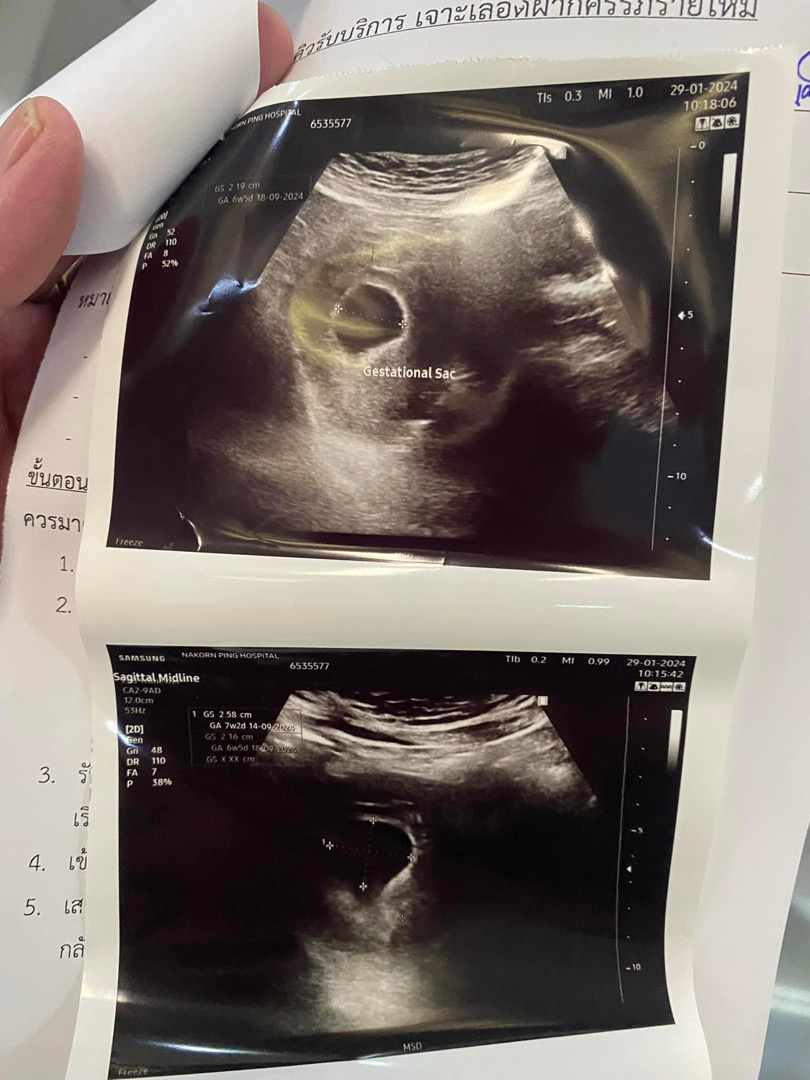

ยังไม่เห็นน้องเห็นแต่ถุงการตั้งครรภ์

อัลตร้าซาวด์ทางไหนคะ ของเราไปครั้งแรกซาวด์หน้าท้อง5wเตอแค่จุดๆ หมอนัดให้มาใหม่อีก2สัปดาห์ ไปตรวจใหม่ซาวด์ทางช่องคลอด(เปลี่ยนคลินิก) เจอน้องพร้อมหัวใจอายุครรภ์ตามอัลตร้าซาวด์6+2w (นับจากปจด วันนั้นต้องเป็น7w)